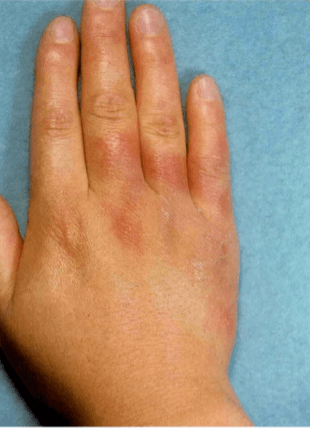

손 봉와직염

손 봉와직염은 다른 부위의 봉와직염과 마찬가지로 손이 붉어 보이며 부종이 생기고 작열감이 생기며 염증의 영향으로 통증 또는 압통이 생길 수 있습니다. 발진이 발생하여 점점 퍼질 수 있으며 증세가 심해지면 발열 및 오한과 같은 전신 증상이 나타날 수 있습니다.